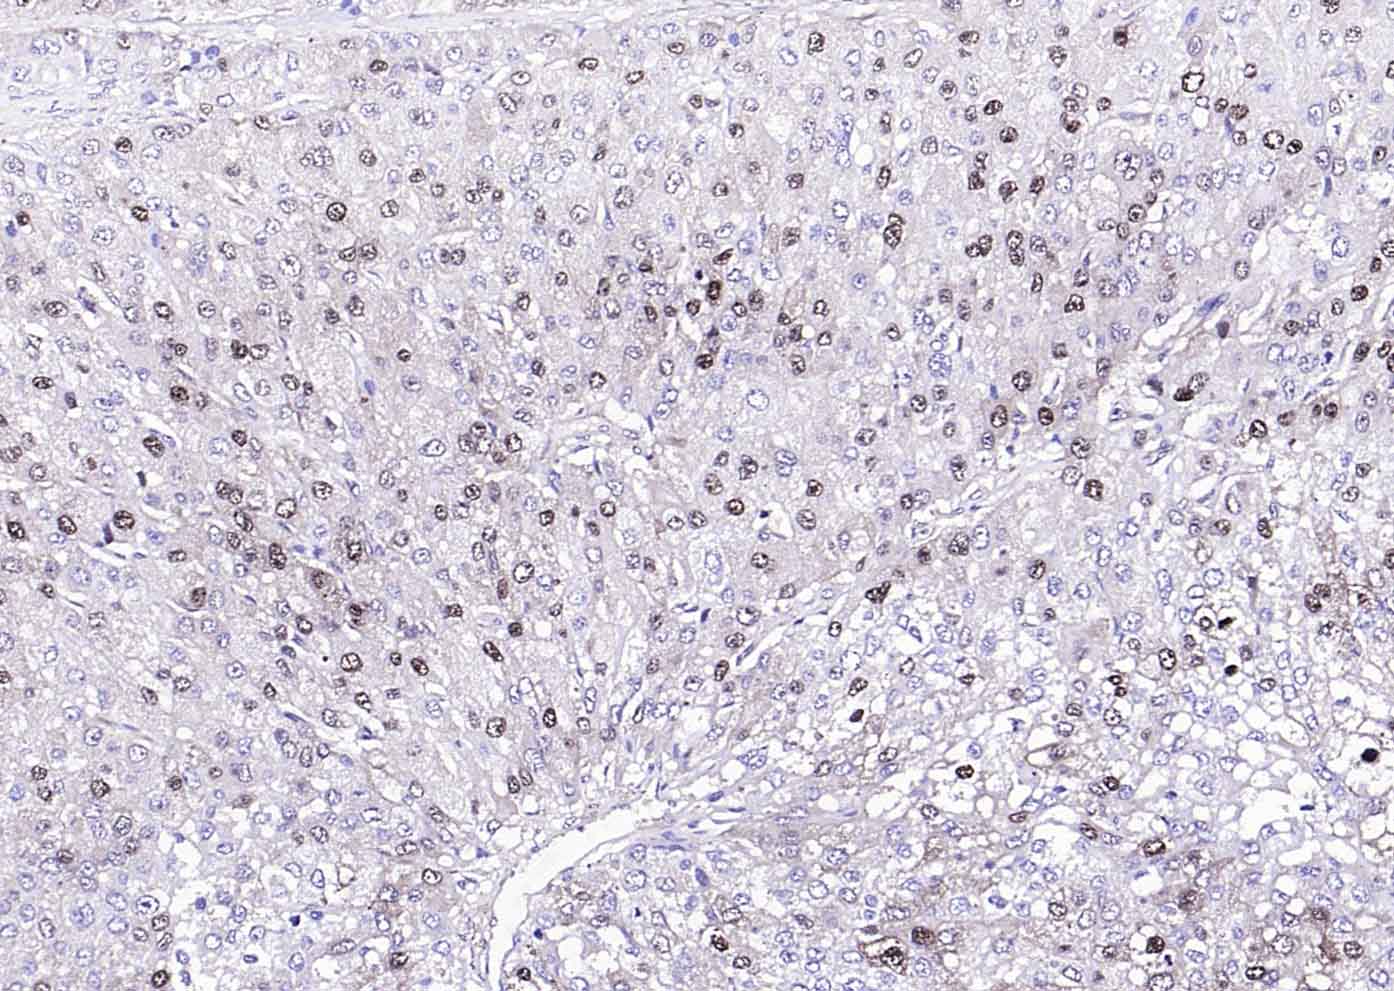

產(chǎn)品圖片

Paraformaldehyde-fixed, paraffin embedded (human liver carcinoma); Antigen retrieval by boiling in sodium citrate buffer (pH6.0) for 15min; Block endogenous peroxidase by 3% hydrogen peroxide for 20 minutes; Blocking buffer (normal goat serum) at 37°C for 30min; Antibody incubation with (Arginase 1) Polyclonal Antibody, Unconjugated (bs-8585R) at 1:200 overnight at 4°C, followed by operating according to SP Kit(Rabbit) (sp-0023) instructionsand DAB staining.

Tissue/cell: human liver carcinoma; 4% Paraformaldehyde-fixed and paraffin-embedded; Antigen retrieval: citrate buffer ( 0.01M, pH 6.0 ), Boiling bathing for 15min; Block endogenous peroxidase by 3% Hydrogen peroxide for 30min; Blocking buffer (normal goat serum,C-0005) at 37℃ for 20 min; Incubation: Anti-Arginase 1 Polyclonal Antibody, Unconjugated(bs-8585R) 1:200, overnight at 4°C, followed by conjugation to the secondary antibody(SP-0023) and DAB(C-0010) staining